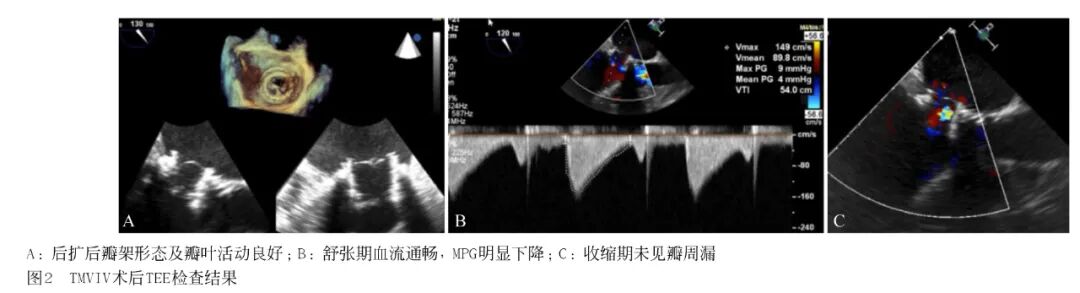

1.3 手术过程 手术在杂交手术室进行,患者行全麻插管,取仰卧位,透视下定位心尖部,在左侧第5 肋间腋中线做5 cm长的切口,进入胸腔悬吊心包。在心尖区缝制荷包,全身肝素化0.8~1.0 mg/kg,激活全血凝固时间维持250~300 s。在双层荷包中央进行穿刺,置入Cordis导丝通过二尖瓣生物瓣进入左心房,见图1A。置入6F猪尾导管,交换预先塑形Lunderquist超硬支撑导丝,在心尖和左心房跨二尖瓣生物瓣形成支撑轨道,采用24F大鞘扩张心尖穿刺点后退出,见图1B、图1C、图1D。在冰水中反向安装25 mm J-Valve瓣膜,通过超硬导丝置入装有瓣膜的输送器(27F),调整输送鞘和原生物瓣膜的同轴性,在左心室内展开定位件后向左心房方向推送,使3 个定位件分别落座于生物瓣3 个瓣脚之间。调整输送器进入左心房的合适深度(一般为介入瓣膜支架最大高度的10%~20%),使介入瓣膜最高点超过生物瓣瓣环平面半个菱形格左右。定位后在快速起搏下使介入瓣膜平稳展开,见图1E、图1F。确定位置正常后释放瓣膜,逐步退出输送器。经食管超声心动图(trans esophagealechocardiography, TEE)和左心室造影检查,确定瓣膜位置、功能正常,有少量瓣周漏。置入微创球囊(26 mm)至原生物瓣瓣环水平进行后扩,瓣周漏消失,撤出导丝,打结止血并放置胸腔引流管,逐层缝合胸壁切口。

TEE显示J-Valve瓣架位置良好,瓣叶开放活动度正常,左房内压力为16 mmHg,较术前(44 mmHg)明显下降;TEE示舒张期前向流通畅,峰值流速及平均压差较术前明显降低,未见瓣周漏,见图2;次日复查TTE:MPG=4 mmHg(术前10 mmHg),患者临床症状缓解,复查胸片较术前改善。